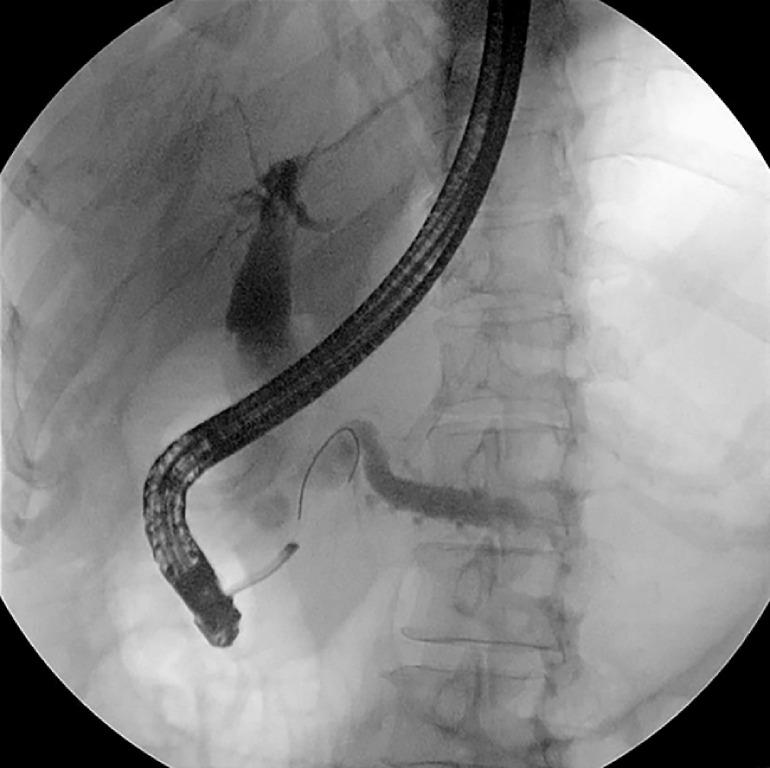

Multiple pancreaticobiliary fistulas combined with acute necrotizing pancreatitis: a rare complication of pancreatic extracorporeal shock wave lithotripsy.

摘要